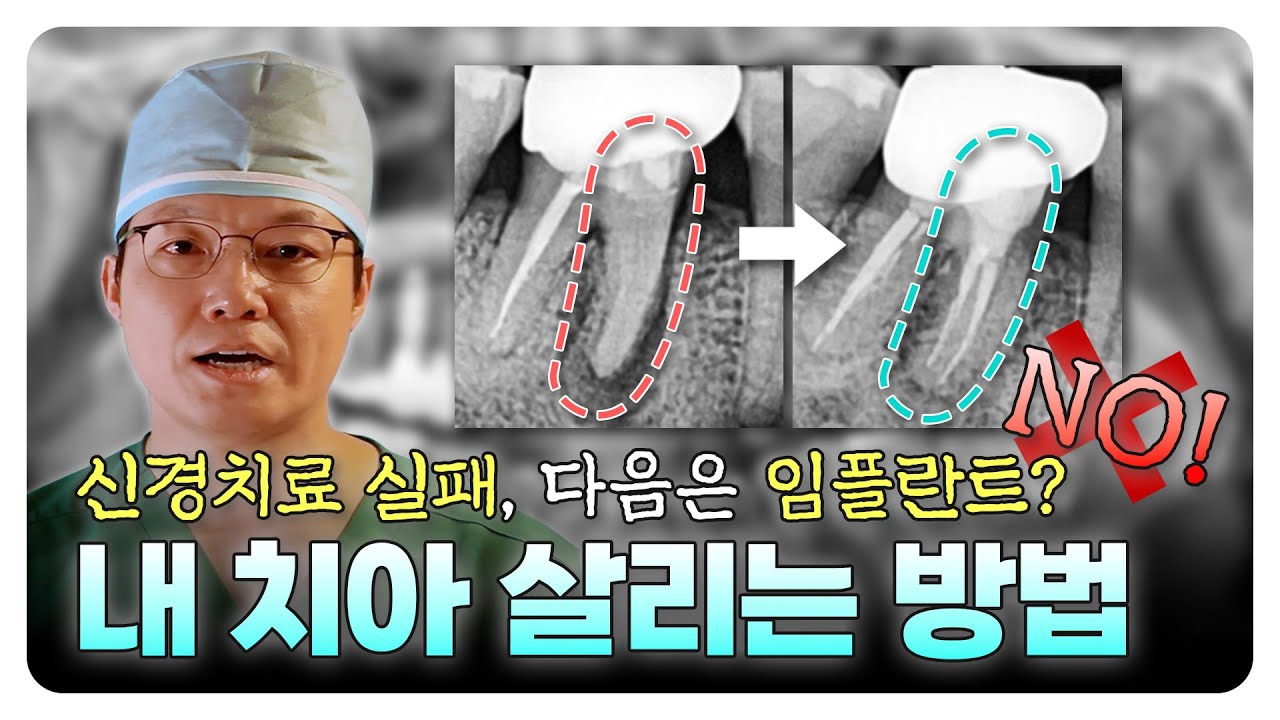

'과거 이미 신경치료를 받았는데, 그 신경치료가 실패해 염증이 생긴 거면

다음 스텝으로 발치하고 임플란트로 가는 게 당연한 거 아니냐' 라고 대부분 이야기하시는데요.

하지만 중요한 건 신경치료가 다 똑같은 신경치료가 아니라는 겁니다.

1. 신경치료 후에도 통증이 있다고 해서 무조건 발치하지 마세요.

치료의 정밀도, 재감염 여부, 치근의 상태에 따라 자연치 보존 가능성은 충분히 있습니다.

또한 기존 신경치료의 품질을 평가할 수 있는 신경치료에 풍부한 경험이 있는 전문의를 찾아가는 것이 중요합니다.

경험많은 전문의가 기존 신경치료의 품질을 판단한 뒤, '기존 신경치료의 품질이 나쁘지 않아, 재치료에 의미가 없다'고 판단할 때 그때 다른 대안을 고려하실 수 있습니다.

다만 기존 신경치료의 품질을 평가받아본 뒤, 문제가 있다면 재치료를 통해 개선될 가능성이 많으니 꼭 발치 후 임플란트만을 고려하지는 않으셨으면 합니다.